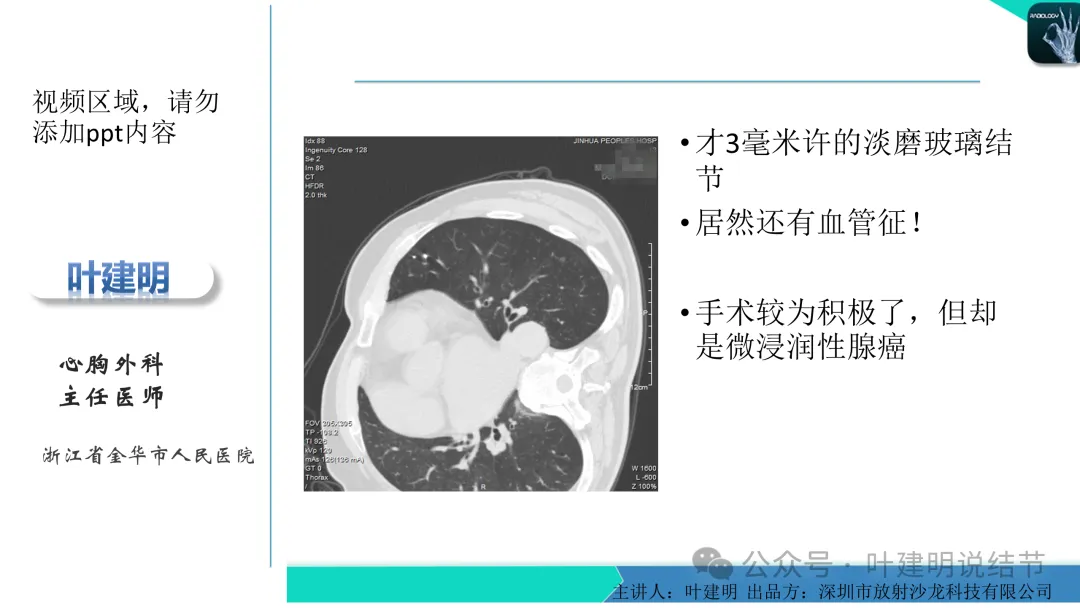

早在2020年时,我受邀在《放射沙龙》做过一个系列的精品课,当时专门总结分析过各类良恶性肺结节与肿块的影像特征,这是当时关于微浸润性腺癌影像特征的分析,今天看来仍基本不太需要改变,大家有兴趣的可以参考: